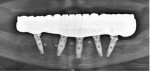

Several hours later the dental team received the STL file, from which they would print the maxillary prosthesis on a 3D printer (Pro 55S) using appropriately colored nanoceramic resin (OnX). The prosthesis was stained and glazed, and metal cylinders were inserted into the undersurfaces of the screw-access holes, each of which was specifically located to fit on the multi-unit abutments (Figure 16 and Figure 17).

The prosthesis fit precisely on the multi-unit abutments, and multi-unit screws were used to secure the prosthesis in place at 20 Ncm (Figure 18 through Figure 20). The screw-access holes were filled, and the patient was instructed in dietary restrictions and adherence to a soft diet. Instructions for oral hygiene were given, and the patient was advised to use a water flosser daily. Analgesics included Motrin 800 mg, and for antibiotics, amoxicillin 500 mg three times a day was prescribed.

Postoperative x-rays documented the full seating of the prosthesis on the multi-unit abutments (Figure 21 and Figure 22). The patient returned at 1-week postoperative for a follow-up visit and to review home care. She remarked that the restoration was comfortable and that she was free of discomfort and extremely pleased with the makeover she received in one day.